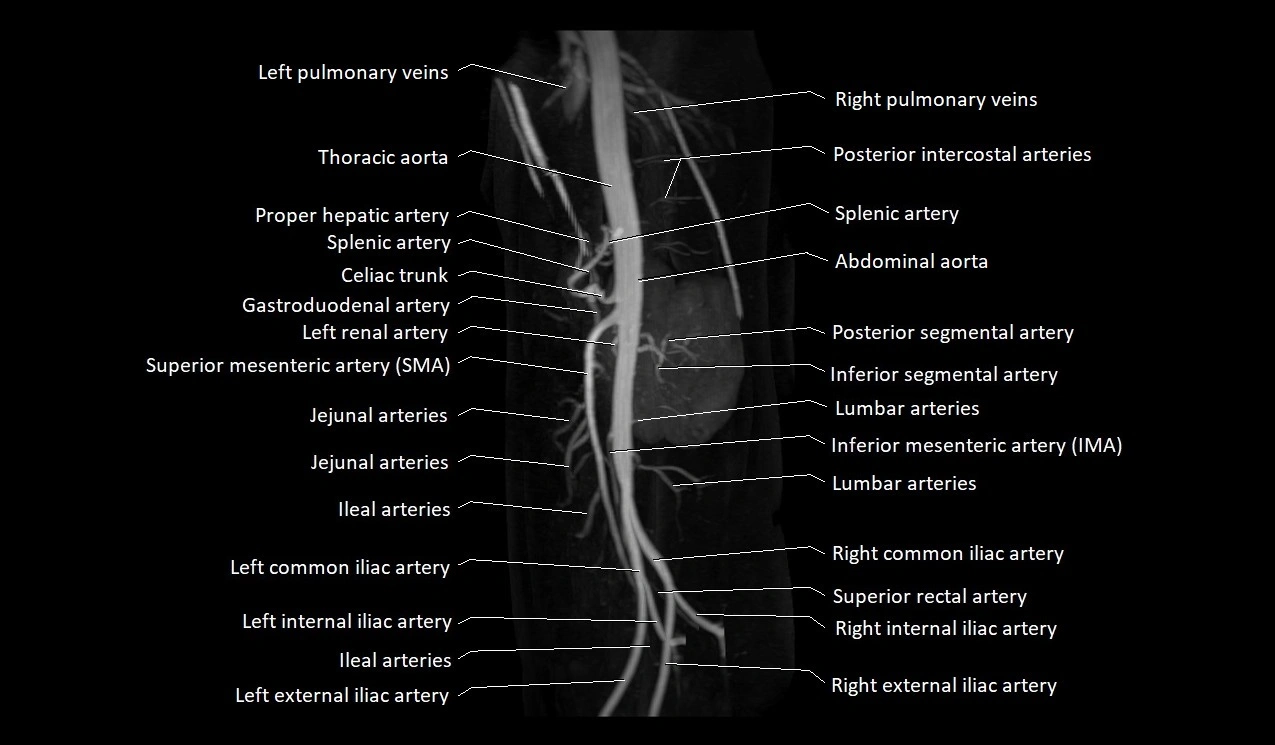

MRA Pelvis with Gadolinium:

-

Clearly delineates the origin, course, and anastomoses of the accessory obturator artery

Identifies connection with inferior epigastric artery, external iliac artery, or obturator artery

Excellent for detecting vascular variants prior to surgery

Useful in mapping pelvic vasculature in trauma, tumor embolization, or preoperative planning